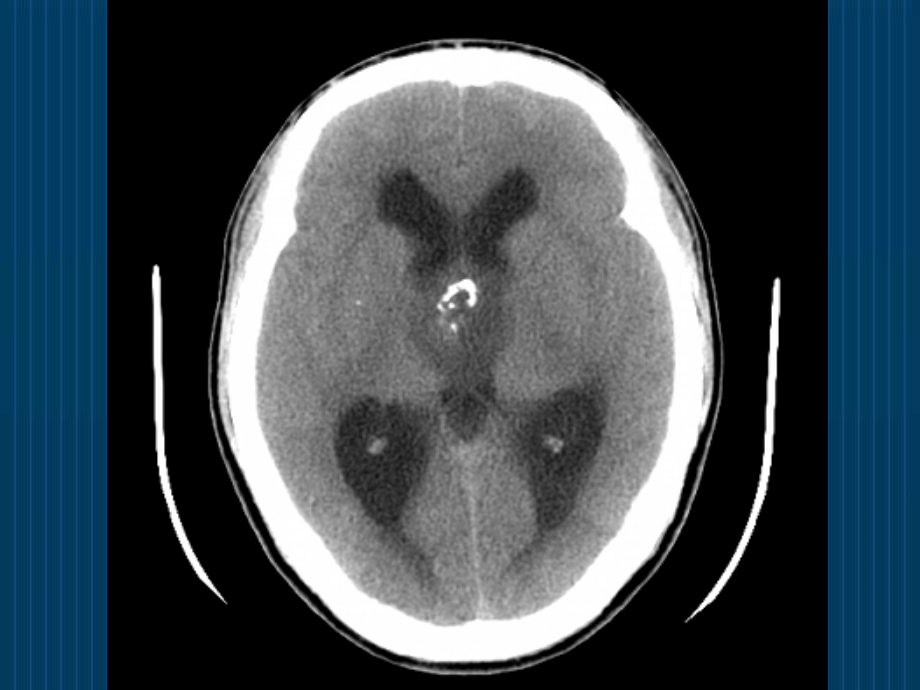

单击此处编辑母版标题样式,单击此处编辑母版文本样式,第二级,第三级,第四级,第五级,*,问题1、,什么样的片子是CT?什么样的片子是MRI?,问题2、,头颅CT与MRI是怎么拍出来的?,CT是怎么拍出来的?,CT(Computerized tomography),原理:X线束透过人体不同密度的组织被吸收的量大小不同,投影到探测器上,转换为数字信号,经电脑处理而获得图像。,黑影低密度区,如脑室;,白影高密度区,如骨骼;,组织对X线的吸收系数称为CT值,水的CT值0HU,骨骼的CT值+1000HU,空气的CT值-1000HU,MRI是怎么拍出来的?,MRI(Magnetic resonance imaging),原理:发射特定频率的射频脉冲激发H原子核,作为小磁体的H原子核可以从射频脉冲中获取能量产生共振,停止发射射频脉冲后,H原子核所吸收的能量逐渐释放,恢复至原来的状态,这个过程所需要的时间有两种,一种是纵向弛豫时间(T1),一种是横向弛豫时间(T2)。由于人体的组织均含有H,2,O和C-H结构,信号强度与H原子核的密度有关,故不同组织有其各自的T1和T2,被探测器所获得,经电脑程序处理形成图像。,问题3、,怎么看CT?,基本信息,1、是否为CT片;,2、分清左右;,3、患者姓名;,4、拍片时间;,5、找病灶,正常头颅CT,眦耳线,层厚8-10mm,常见疾病的CT诊断,大面积脑梗死,常见疾病的CT诊断,基底节区脑梗死,常见疾病的CT诊断,脑出血,常见疾病的CT诊断,脑干出血,常见疾病的CT诊断,颅内肿瘤,问题4、,怎么看MRI?,基本信息,1、是否为MRI片;,2、分清T1、T2;,3、患者姓名;,4、拍片时间;,5、找病灶,常见疾病的MRI诊断,略,